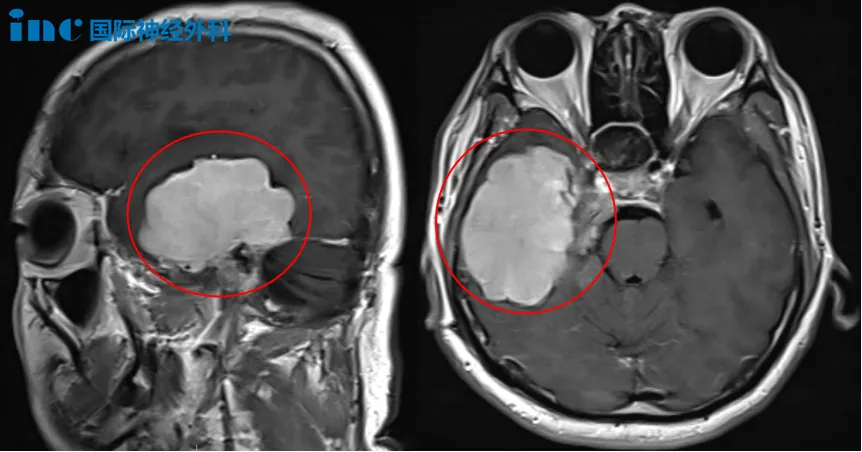

術前MRI

“必須高質量地活著!”雖然沒有癥狀,但膠質瘤可能長大、甚至惡化,鄭先生毅然決定盡早手術,以絕后患。他做出這一堅定選擇的信心,正來源于對巴教授深厚的信任。

術前談話時,巴教授表示已經(jīng)通過特殊技術處理腦成像,以明確腫瘤位置及與運動神經(jīng)纖維束的關系,如同繪制大腦中的地圖一樣。他強調,由于個體差異,術前充分了解這些信息對手術規(guī)劃至關重要。“我們會竭盡所能(try the best)。”這句承諾,也給予了鄭先生莫大的信心。順利手術后,鄭先生無需進ICU。